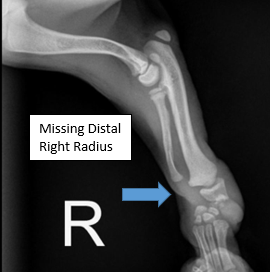

Diagnosis: Radial hemimelia (radial and carpal aplasia)

Assessment: Windsor initially presented to Pawsitive Steps Rehabilitation and Sports Medicine for evaluation of a congenital right forelimb deformity, where a portion of his right radius did not develop. At the time of initial presentation, Windsor was still growing, so a permanent device to correct the deformity was not recommended. Windsor was placed in a temporary splint and bandage until his growth plates solidified. He was then fitted for an orthotic/prosthetic device which allows him to properly posture and bear weight, realigning his anatomy to optimal positioning. Over the past couple of months, Windsor has been acclimating well to device, demonstrating solid mobility and stability. Windsor has also gained muscle mass in his right front limb and has strengthened his core and hindlimb musculature.

- Congenital right forelimb deformity

- Right carpal varus (laxity)